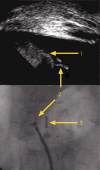

Safe biopsy of aortic masses guided by intraluminal two dimensional ultrasonography